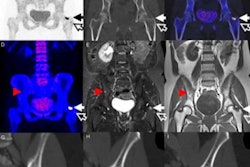

The SNU group developed a hybrid multiplexing approach that replaces the resistors used in resistive charge division (a) and the capacitors in capacitive charge division (b) with a resistor and capacitor in parallel (c). The combination avoids the degradation in SiPM timing resolution seen in (a) and energy resolution in (b). The full hybrid scheme is shown in (d).The second approach replaces the resistors with capacitors. Here, however, the capacitance creates a high-pass filter, distorting the scintillation pulse tail into a negative "undershoot" that degrades the detectors' energy resolution. In a bid to sidestep the limitations of the two approaches, the researchers replaced the individual resistors and capacitors with pairs of parallel resistors and capacitors.

Uniform pulses produced across the detector array resulted in a high correlation between time-over-threshold (ToT) and the integrated charge per pulse, indicating the ToT technique's feasibility ((a) resistive, (b) capacitive, and (c) hybrid circuits). Flood histograms generated with the ToT readout demonstrated that distortions of the crystal map produced by the resistive (d) and capacitive (e) networks were markedly mitigated using the hybrid network (f).The measurements revealed the hybrid network had good energy and time resolution. The one-to-one SiPM-crystal configuration, for example, had an energy resolution of 10.7 ± 0.5% and a coincidence resolving time (CRT) of 388 ± 17 ps in the one-to-one crystal-SiPM coupling. The network inherited the timing resolution of the capacitive network, while energy resolution in the three networks was comparable.